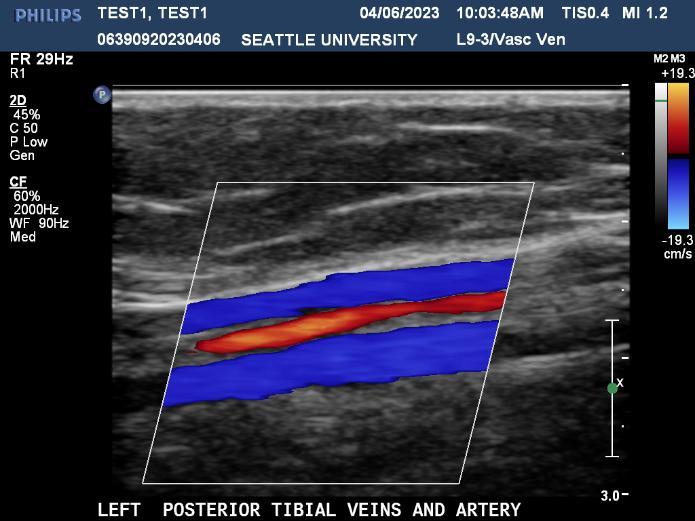

Ultrasound is a non-invasive diagnostic tool that uses high-frequency sound waves to propagate images of organs and tissues within the body. The Diagnostic Ultrasound program at Seattle University offers three distinctive track specializations in General (abdomen extended, OB/GYN) Vascular and Cardiac sonography.